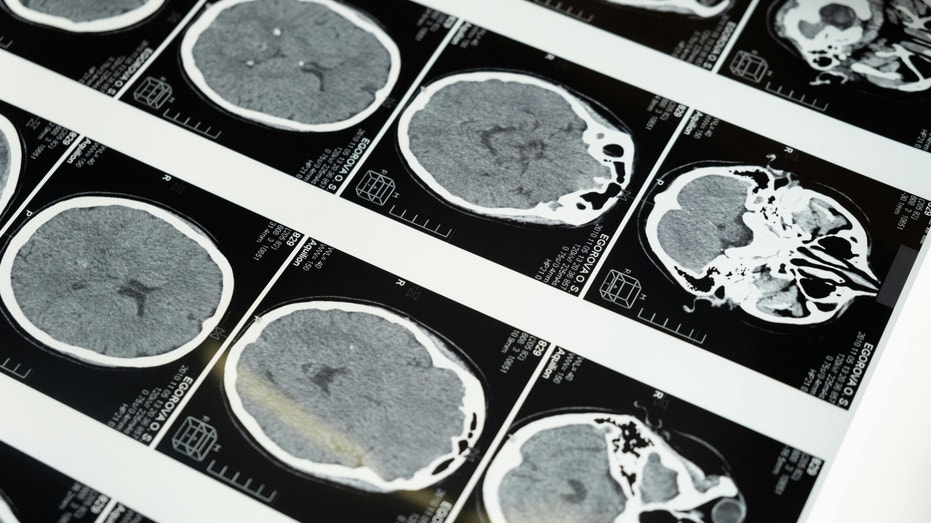

Yes, the same basic technology is used in medical imaging. But this time, it targets neural circuits.

Most brain-computer interface systems rely on electrodes that detect electrical signals from neurons. Neuralink is the most visible example. It places tiny threads inside the brain to record activity. Ultrasound works differently.

Instead of measuring electrical signals directly, it uses high-frequency sound waves. Depending on intensity and focus, those waves can:

Ultrasound faces technical limits. First, the skull weakens and distorts sound waves. That makes it harder to obtain precise signals. In research settings, detailed readouts of neural activity have required special implants that allow ultrasound to pass more clearly than bone.

Second, ultrasound measures changes in blood flow. Blood flow shifts more slowly than electrical firing in neurons. That delay may limit applications that require fast, detailed signal decoding, such as real-time speech translation. In short, stimulation is one challenge. Accurate readout is another level entirely.